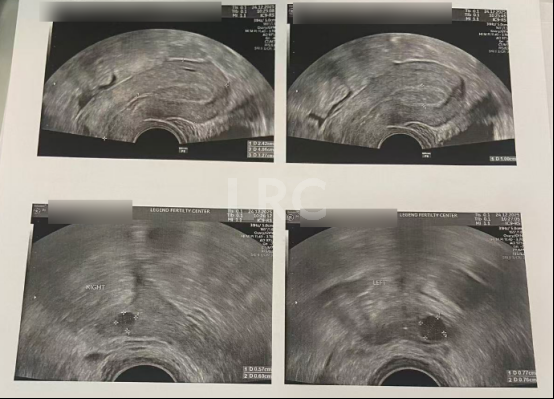

促排第三天

阴超检查:

- 右侧卵泡 2 颗 (9,4mm)

- 左侧卵泡 2 颗 (11,5mm)

子宫内膜厚度:4.2mm

阴超监测到新增 2 枚小卵泡,形成大卵泡+小卵泡的发育梯队。医生继续沿用温和刺激方案,通过口服药持续唤醒潜在卵泡,计划后续采用“黄体期促排 + 连续取卵”策略,较大化收获可用卵子。